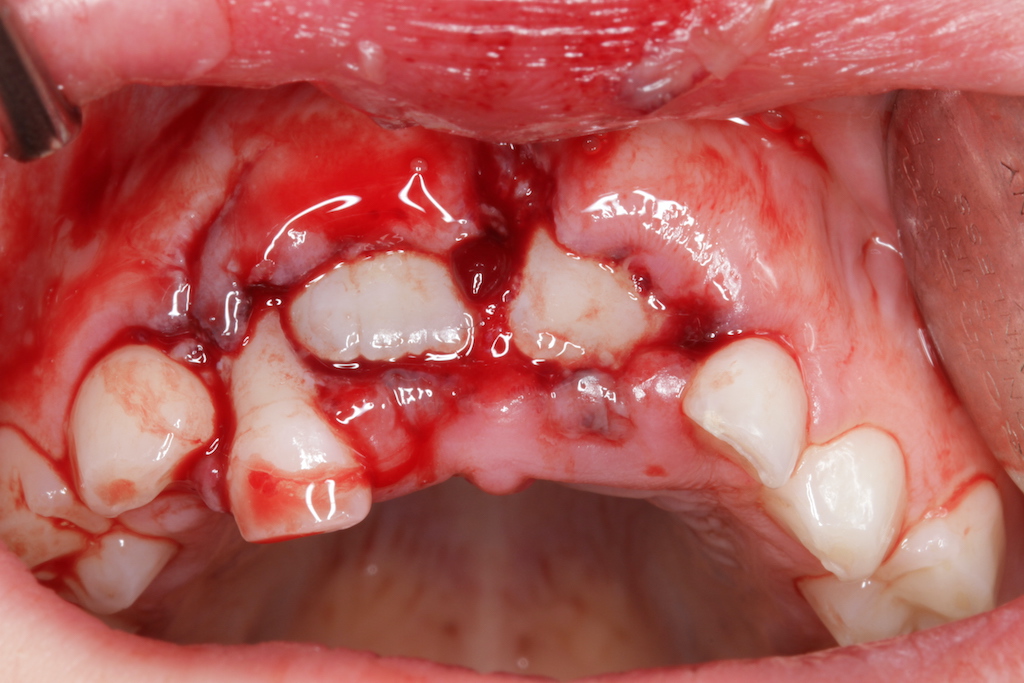

Insbesondere bei schwerwiegenden Verletzungen parodontaler Strukturen (Intrusionen und Avulsionen) ist mit einer hohen Gefahr von externen Wurzelresorptionen zu rechnen. Hier liegt die Förderung von Wundheilungsvorgängen der verletzten Gewebe im Fokus aller therapeutischen Bemühungen. Zellphysiologische Lagerungsmedien, Tetrazykline, Steroide, Schmelz-Matrix-Proteine und biokompatible Materialien sind einzelne Puzzleteilchen die sich zu neuen Therapiekonzepten ergänzen und in komplexen Fällen über Zahnerhalt oder Verlust entscheiden können.